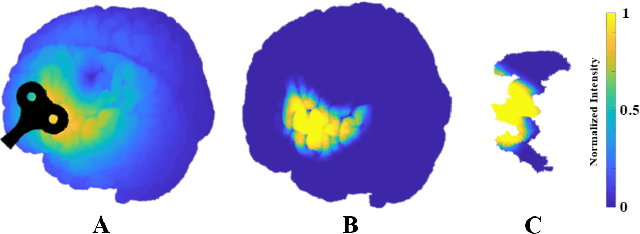

Abstract:Post-traumatic epilepsy (PTE) is a life-long complication of traumatic brain injury (TBI) and is a major public health problem that has an estimated incidence that ranges from 2%-50%, depending on the severity of the TBI. Currently, the pathomechanism that in-duces epileptogenesis in TBI patients is unclear, and one of the most challenging goals in the epilepsy community is to predict which TBI patients will develop epilepsy. In this work, we used diffusion-weighted imaging (DWI) of 14 TBI patients recruited in the Epilepsy Bioinformatics Study for Antiepileptogenic Therapy (EpiBioS4Rx)to measure and analyze fractional anisotropy (FA), obtained from tract-based spatial statistic (TBSS) analysis. Then we used these measurements to train two support vector machine (SVM) models to predict which TBI patients have developed epilepsy. Our approach, tested on these 14 patients with a leave-two-out cross-validation, allowed us to obtain an accuracy of 0.857 $\pm$ 0.18 (with a 95% level of confidence), demonstrating it to be potentially promising for the early characterization of PTE.